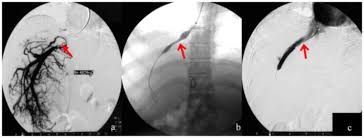

Located in metro Denver northern Colorado and western Nebraska serving all of the Front Range our team consists of board-certified and fellowship-trained interventional radiologists. Toxic injury to liver sinusoids causes sloughing of endothelial cells that embolize to hepatic venules and cause eventual fibrosis of the venules. Such as a TIPS are most often performed by a specially trained interventional radiologist in an interventional radiology suite or occasionally in the operating room.

Some interventional radiologists prefer performing this. Le syndrome myéloprolifératif est la cause la plus fréquente de syndrome de Budd-Chiari 40-50.